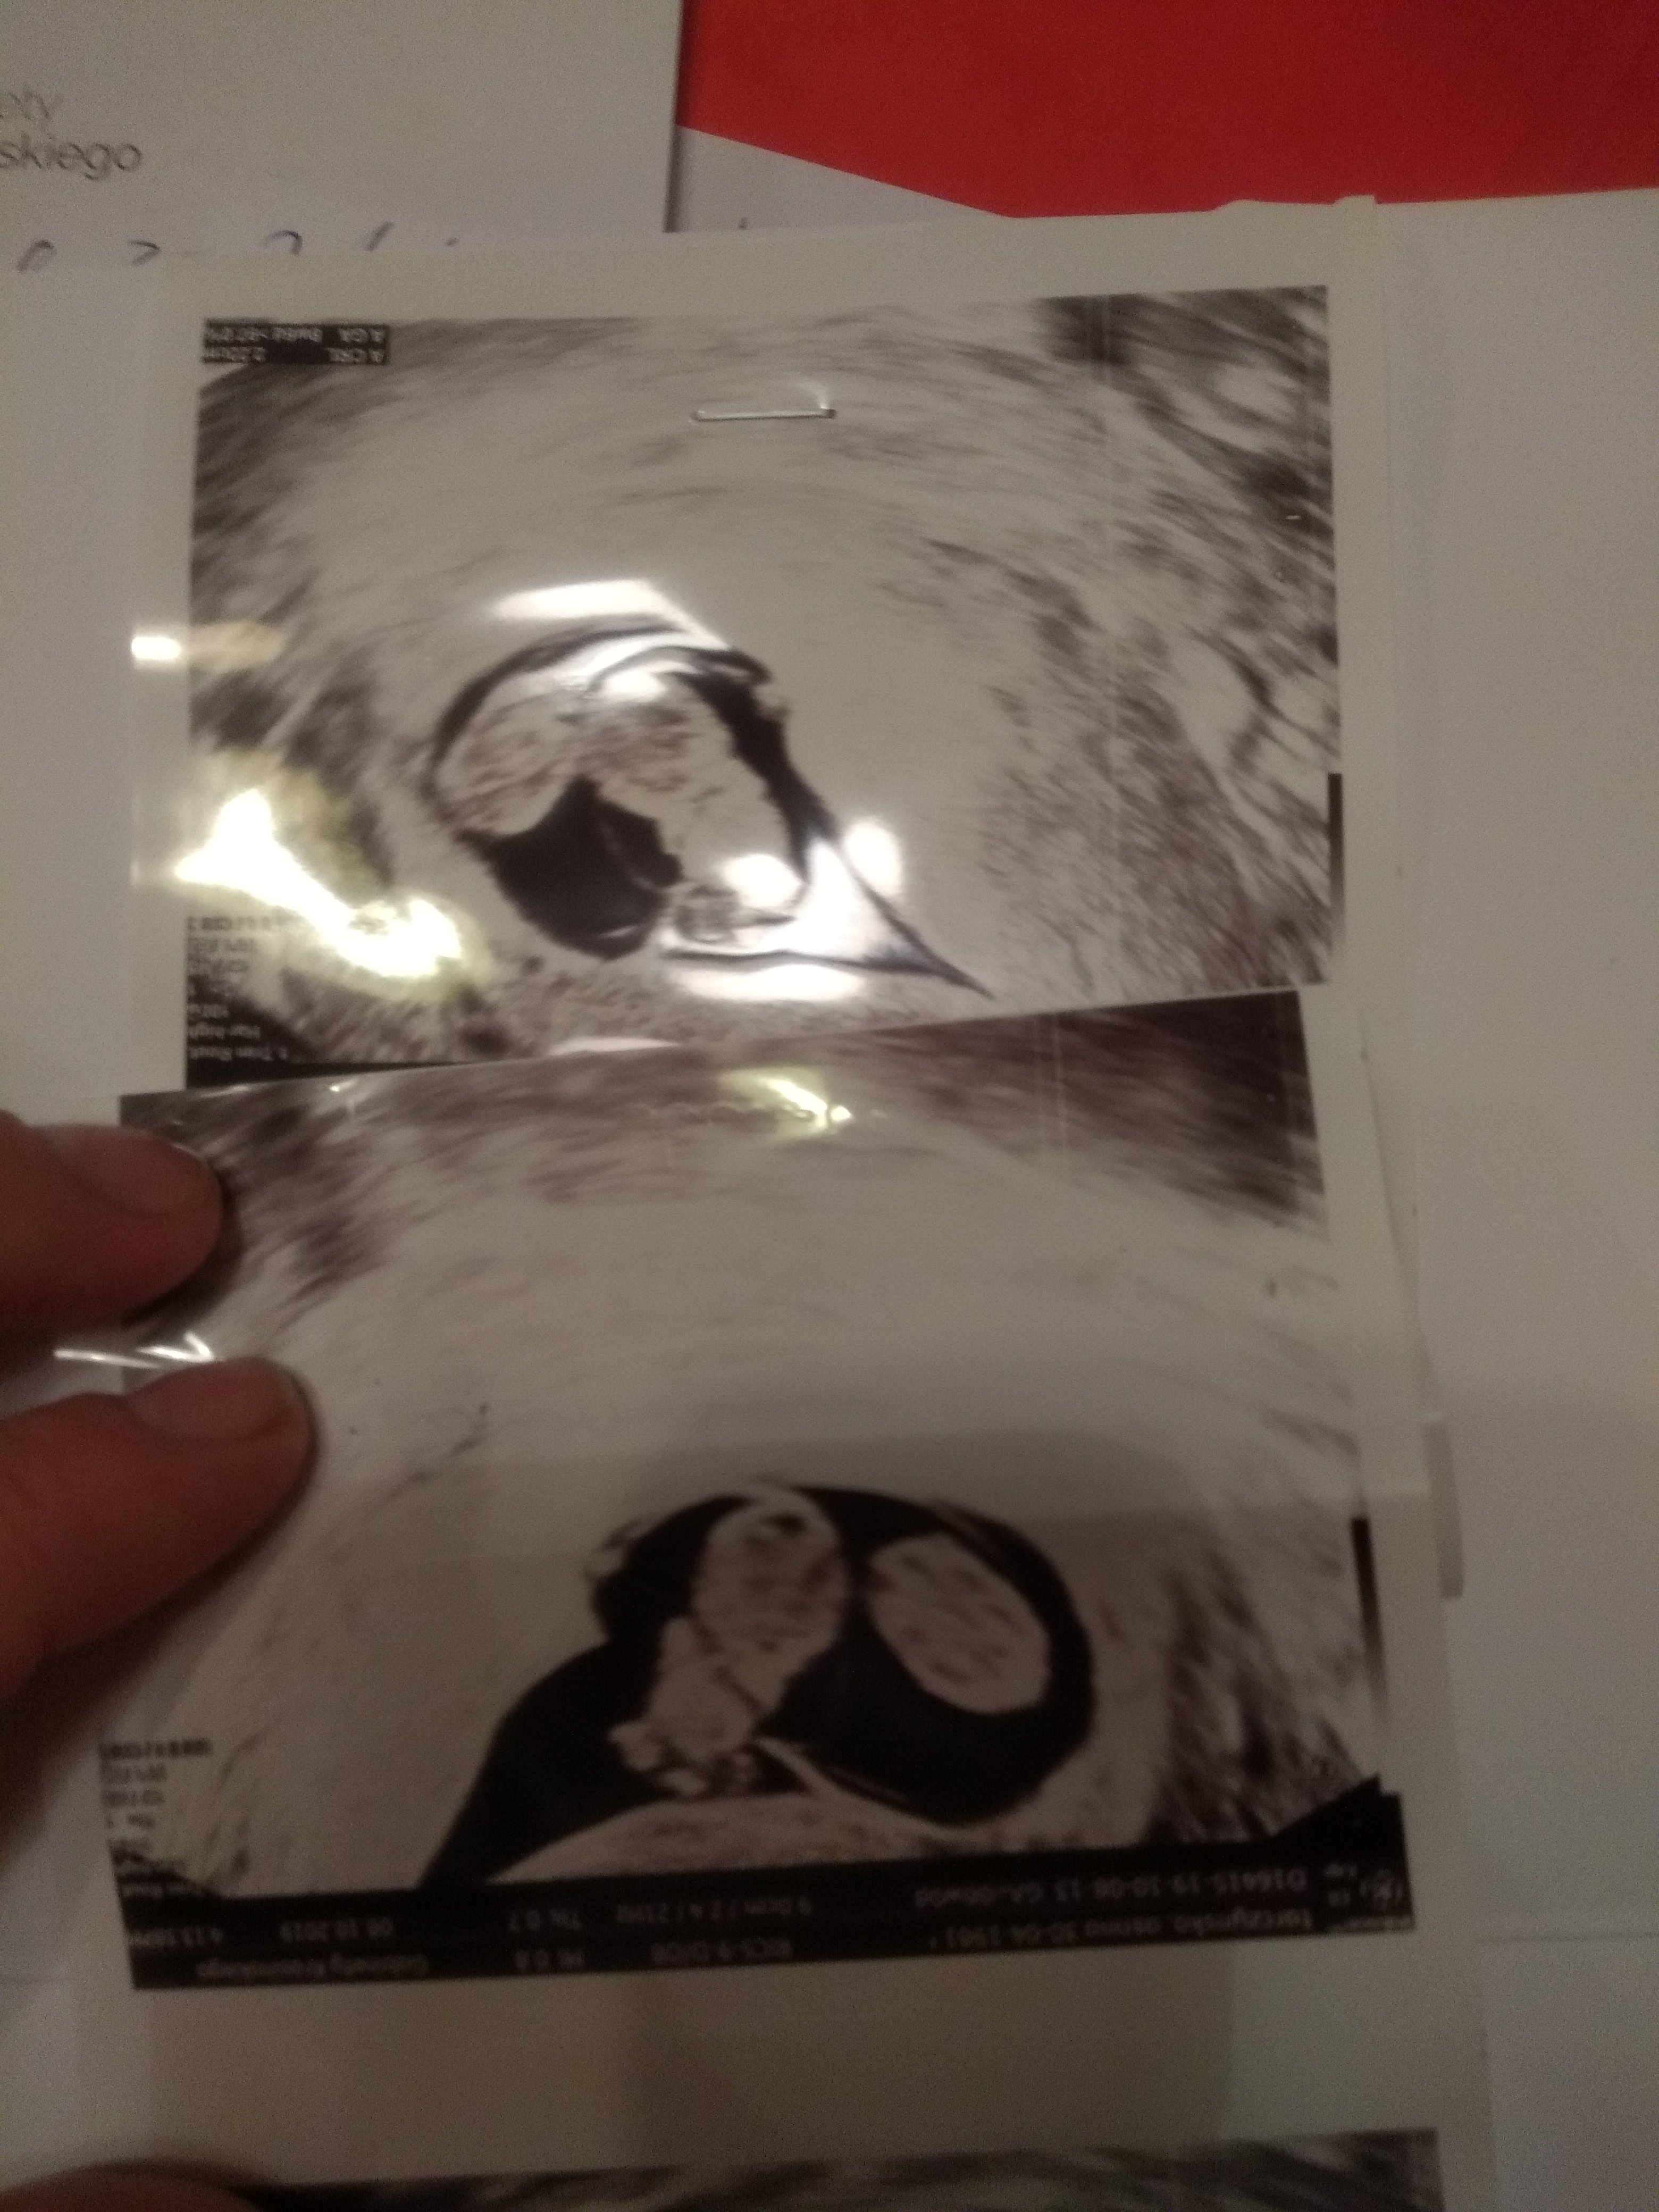

U mnie wszystko dobrze :) dostałam kartę ciąży. Dzieciaczki mają równo po 2,2cm i są dwuowodniowe jednokosmówkowe. Tylko serduszka biły im szybko bo 195 ale lekarz mówi że to w normie. Na razie wszystko rozwija się dobrze. Kolejna wizyta za 3 tygodnie. Śmiesznie leżą tak pod kątem prostym do siebie i głowy mają obok siebie. Miśki Haribo takie.